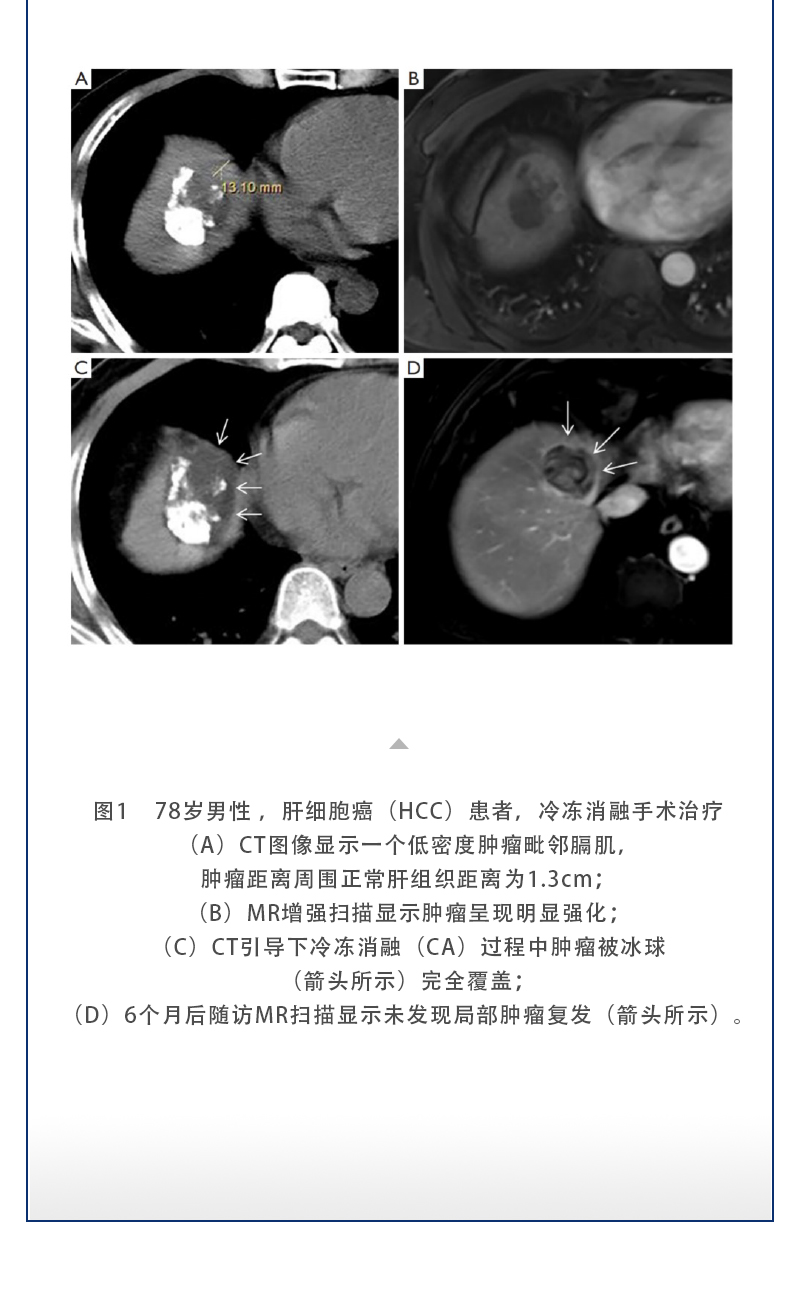

【HYGEA·科研資訊】冷凍消融治療肝癌

發(fā)布時間:2025-09-05 | 作者:海杰亞 | 瀏覽次數(shù):139